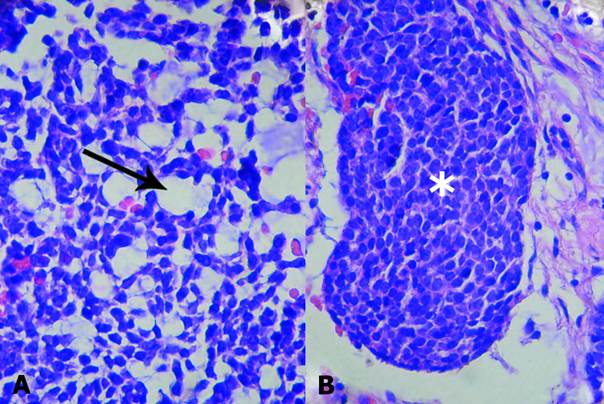

In the tubular pattern there were basaloid cell islets that contained pseudocysts or prominent lumen lined with cuboid cells (Fig. 1A and B).

The diagnosis of mixed type basal cell adenocarcinoma was made on the basis of its histological patterns (solid and tubular) and its malignant character, with an aggressive growth with infiltration of the tumor capsule and periparotid fat, perineural invasion and metastasis of a regional lymphoid node (Fig. 2A, B and C).